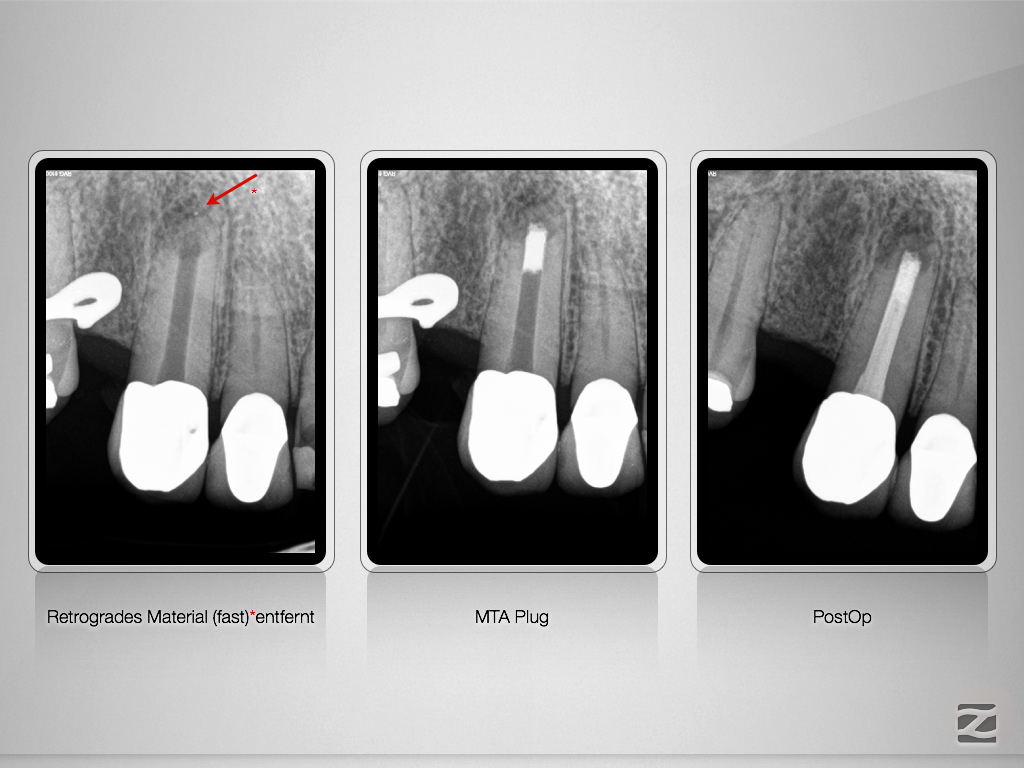

13D.007

Ketac Silver retrograd